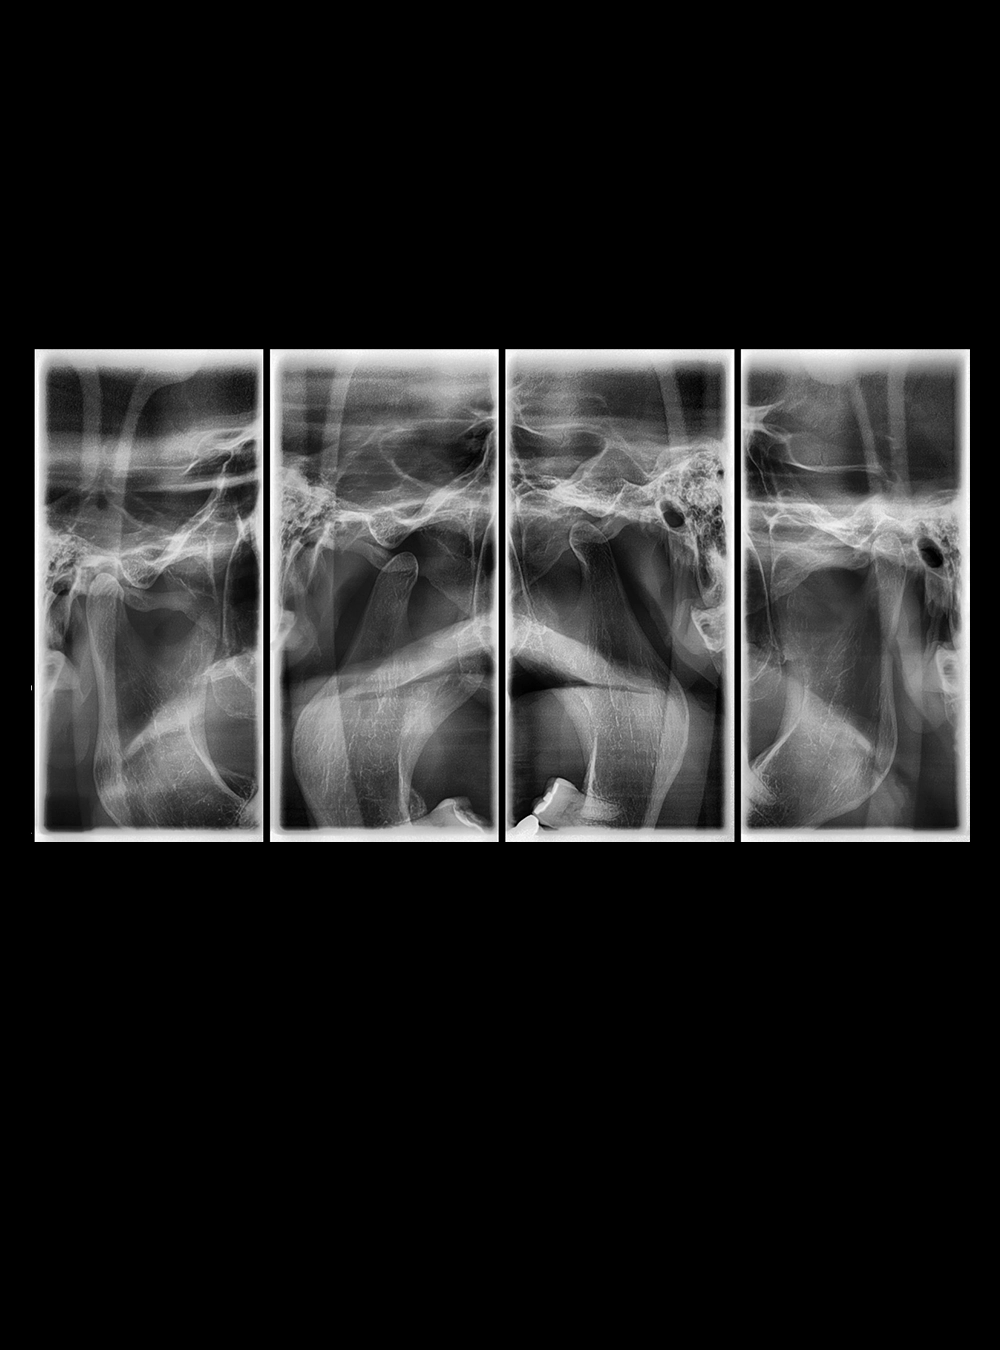

Tomografías ATM

Rx ATM Lateral Comparativa

• Atm Lateral Comparativa